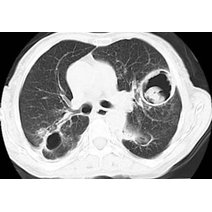

白肺的意思是指胸片、CT上发现正常肺组织透X线是黑色,只有心脏和大血管是白色,但是由于各种疾病、各种致病因素,导致两肺野呈大片的密度增高,出现白色的阴影,就...47600人收听

白肺一般是指重症肺炎在X光检查下的表现,肺部呈现一大片的白色状态而闻名。形成白肺一般都预示着肺部被炎症所广泛浸润,引起白肺的病因往往非常复杂,并且来势凶...28117人收听

白肺是指患者在X光胸片检查或者肺部CT检查中,肺部间质组织呈现大片状白色状病变的表现。白肺的症状表现多发生于重症肺炎,因为肺部间质组织持续性受到病毒、细...60057人收听

白肺(White lung)是一种临床综合症,其特征是重度肺炎患者的肺部积累了大量渗出物,影响多个肺叶,使肺部影像学检查呈现出大范围的白色区域。病因多为新型冠状病毒感染、细菌性肺炎、中东呼吸...

[最佳答案] 白肺是放射学名词,所谓白肺是指胸片或者CT上弥漫的高密度影,使得片子看不到肺纹理。导致白肺发生的原因很多,常见的大叶性肺炎、肺水肿,或者是病毒性肺炎比如SARS,以及流感、病毒引起的肺炎都会导致白肺。 至于能不能治愈要根据疾病的不同来决定, 白肺是放射学名词,所谓白肺是指胸片或者CT上弥漫的高密度影,使得片子看不到肺...